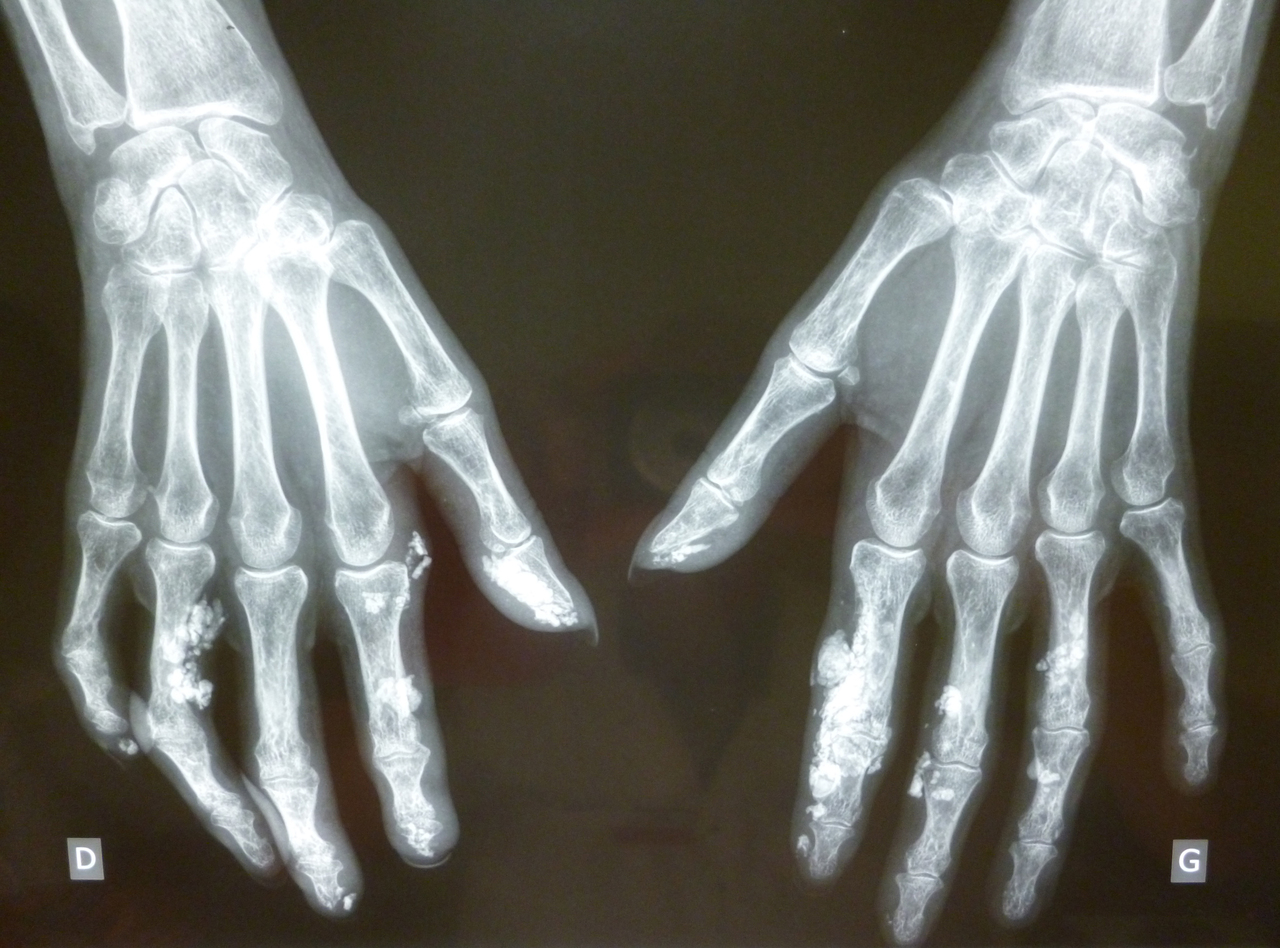

Quel est votre diagnostic ? Calciphylaxie Sclérodermie Dermatomyosite Calcifications post-infiltrations de corticoïdes Granulomes sarcoïdosiques calcifiés OK Pour en savoir plus : Legendre P, Mouthon L. Sclérodermie systémique. Rev Prat 2017;67(7). Valider mes réponses